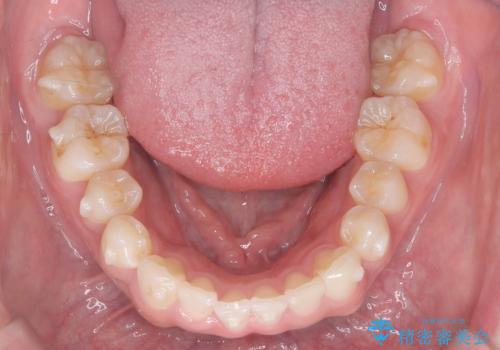

歯のデコボコを治したい|インビザラインで綺麗な歯並びに!|矯正期間は6ヵ月!

- 歯のデコボコが気になるを主訴に来院された患者様です。

インビザラインで歯は抜かずに非抜歯でデコボコを改善しました。

インビザラインで叢生の改善を行いました。

歯は抜かずに、拡大と少しのIPRで並べました。

矯正期間は半年です。

綺麗な歯並びを手に入れ大変ご満足していただきました。